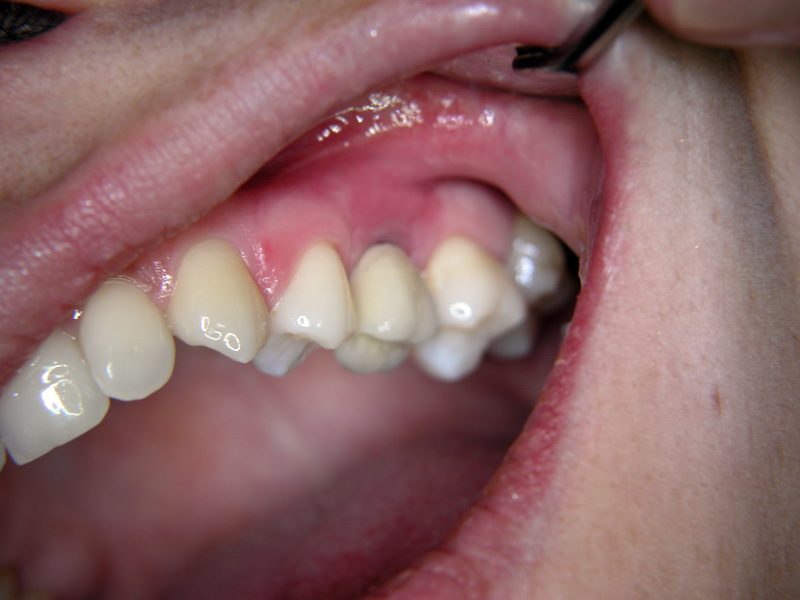

Implante - Galerie Foto

Caz II